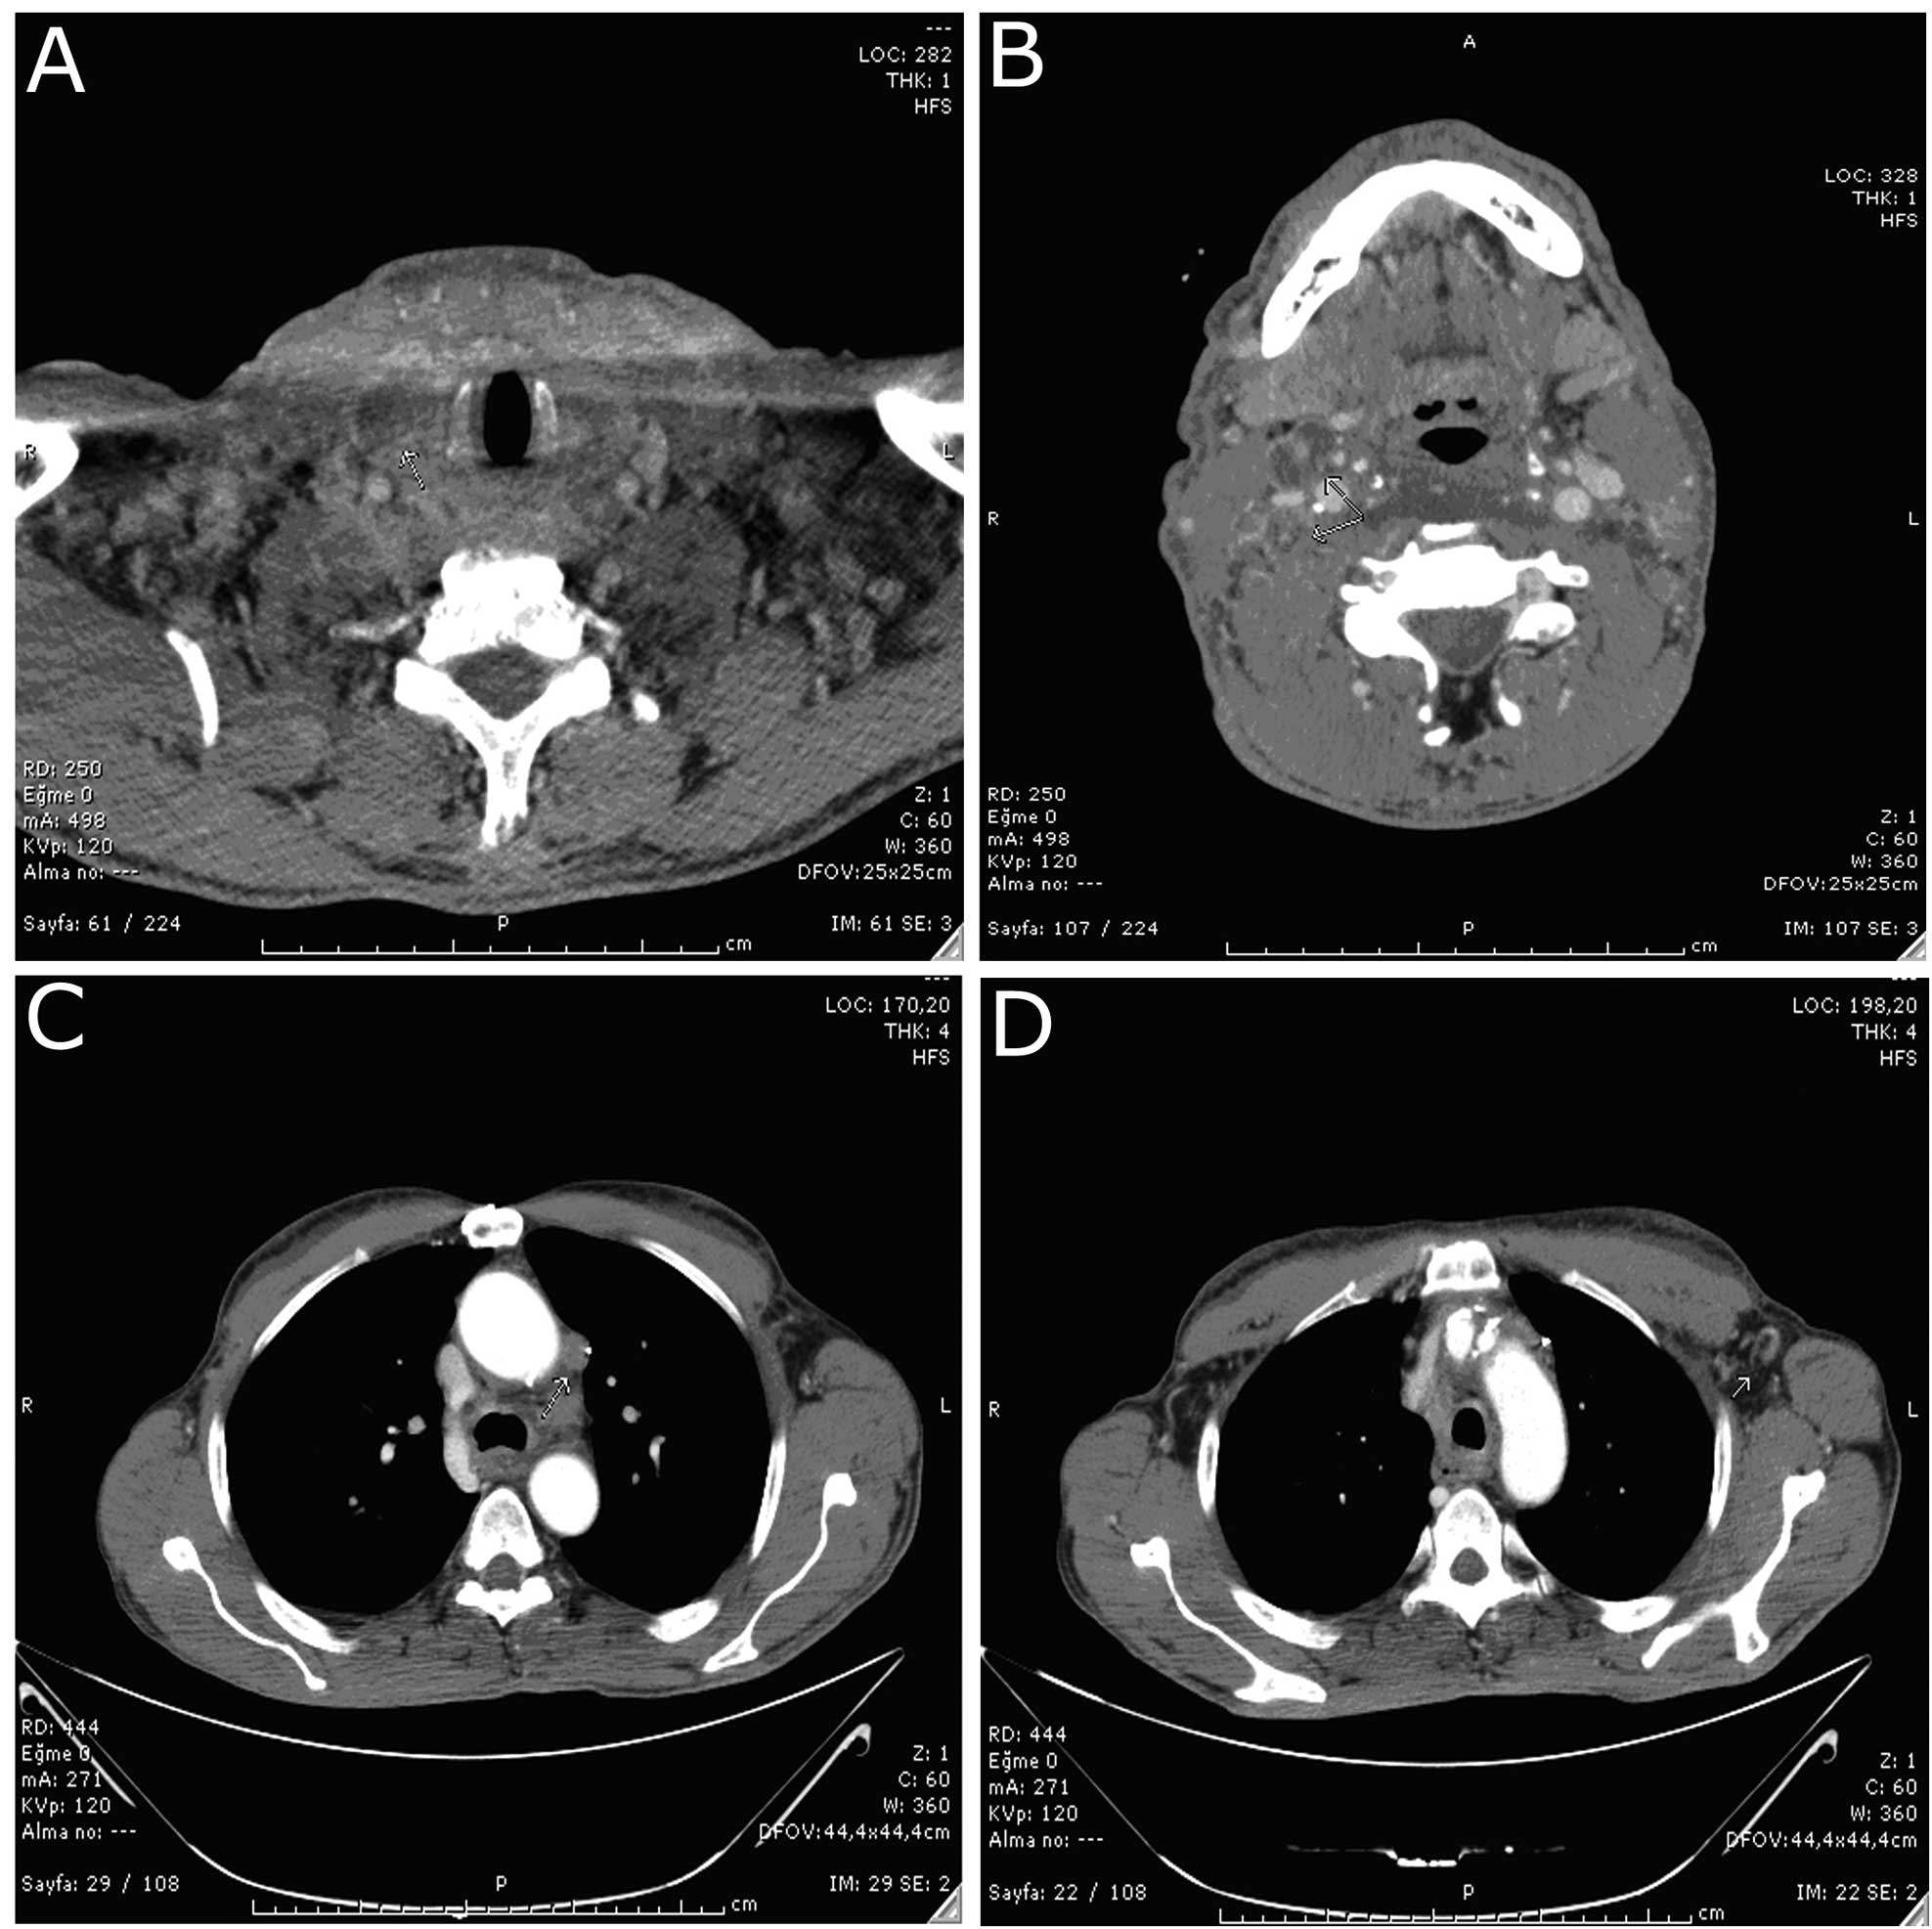

Anaplastic Thyroid Carcinoma With Diffuse Thoracic Skin Metastasis A

Anaplastic Thyroid Carcinoma With Diffuse Thoracic Skin Metastasis A